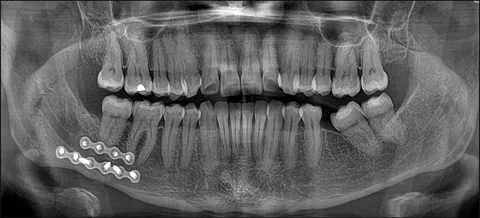

Advanced diagnostic tools, including digital X-rays and Cone Beam Computed Tomography (CBCT) scans, allow dental professionals to accurately evaluate the extent of the damage and develop personalized treatment plans tailored to each patient.

The Role of Radiology in Diagnosing Tooth Fractures

Modern radiological techniques play a critical role in identifying fractures that aren’t visible during a standard examination. Digital X-rays and CBCT scans provide a deeper understanding of the damage beneath the gum line.

This technology allows dental specialists at Royal Cosmetic Surgery to assess whether the fracture has affected the pulp or root, ensuring a targeted and effective treatment plan. Without proper imaging, hidden fractures could worsen and lead to serious complications like infections.